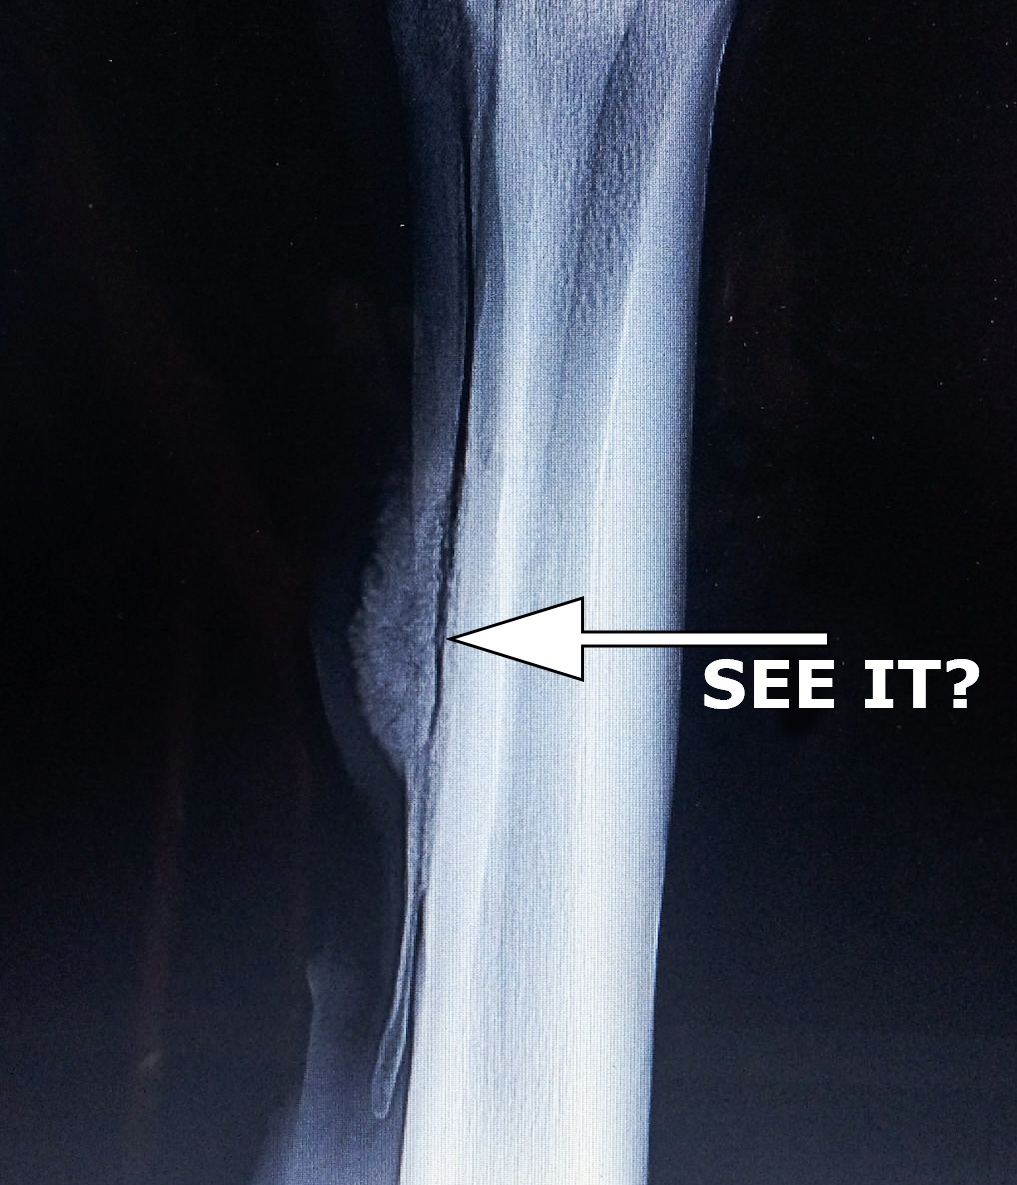

Shin Splints X-Ray . Shin splints are usually diagnosed based on your medical history and a physical exam. ‘shin splints’ is a vague term that implicates pain and discomfort in the lower leg, caused by repetitive loading stress. medical history and physical examination are frequently used to diagnose shin splints. a magnetic resonance imaging (mri) scan is also sometimes used to help to tell the difference between shin splints and. medial tibial stress syndrome (mtss) is a frequent overuse lower extremity injury in athletes and military personnel. There can be all sorts of causes to this pathology.

medical history and physical examination are frequently used to diagnose shin splints. a magnetic resonance imaging (mri) scan is also sometimes used to help to tell the difference between shin splints and. medial tibial stress syndrome (mtss) is a frequent overuse lower extremity injury in athletes and military personnel. There can be all sorts of causes to this pathology. Shin splints are usually diagnosed based on your medical history and a physical exam. ‘shin splints’ is a vague term that implicates pain and discomfort in the lower leg, caused by repetitive loading stress.